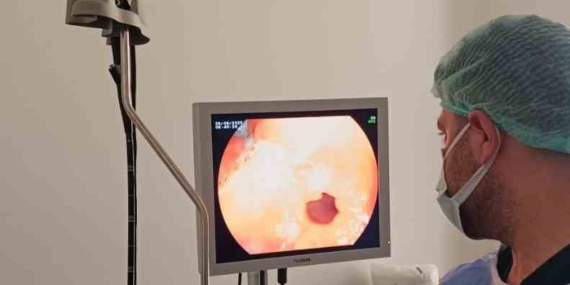

Çermik Devlet Hastanesi’nde Endoskopi ve Kolonoskopi Ünitesi Hizmete Girdi

Çermik Devlet Hastanesi, yeni Endoskopi ve Kolonoskopi Ünitesi ile sağlık hizmetlerini bir adım ileriye taşıyor. Detaylar için tıklayın!